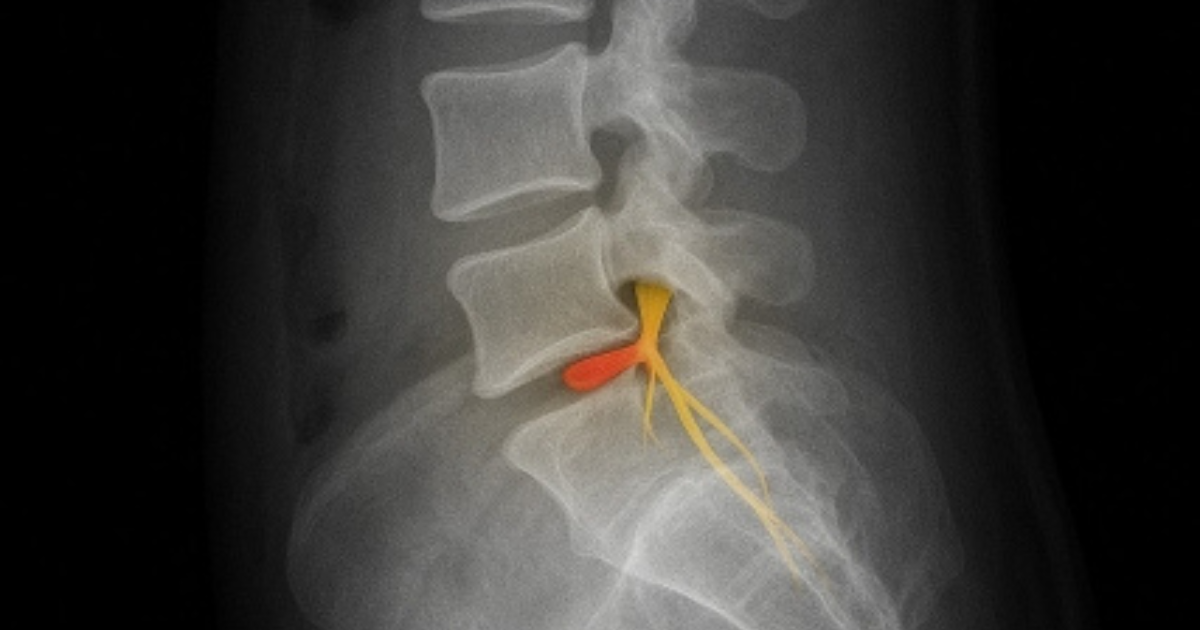

背骨の一つひとつをつなぐ椎間板。

外側は硬い線維輪、中心には80%が水分の髄核が詰まっている。

この構造が、立つ・歩く・衝撃を吸収するためのクッションになる。

■ヘルニアは“結果”。その前段階が「椎間板症」

髄核が線維輪を押し出して飛び出すのが 椎間板ヘルニア

腰椎椎間板症(椎間板の膨隆・変性による痛み)

MRIでは正常なら白く写る椎間板が、

椎間板症やヘルニアでは黒く写ることが多い。

水分が減り、クッション性は低下。

周囲の神経が刺激され、腰以外に痛みが出るケースもある。